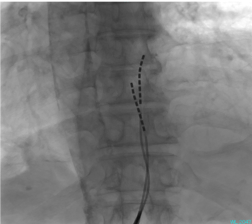

- 難治性の疼痛を伴う重症下肢虚血(足の安静時痛、疼痛を伴う潰瘍)に対する治療法です。脊髄に微弱な電流を流す機械を植え込むことにより、痛みの軽減と末梢血流増加による潰瘍の治癒を目指します。

- 当院では循環器内科、脳外科が協力して積極的に治療に取り組んでおり、血行再建(バイパス手術やカテーテル治療)不可能な患者さんに施行し、非常に良好な結果が得られています。